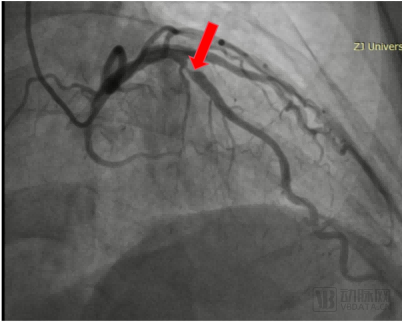

Preoperative angiography showed a lesion with a diameter of 3.50mm, a length of 12mm, a stenosis degree of 90%, and TIMI blood flow grade 3 in the middle segment of the patient's anterior descending artery (LAD). After evaluation by the team of Academician Wang Jian'an, it has been decided to use coronary artery remodeling catheters to treat patients with LAD.

Preoperative angiography of patient's LAD